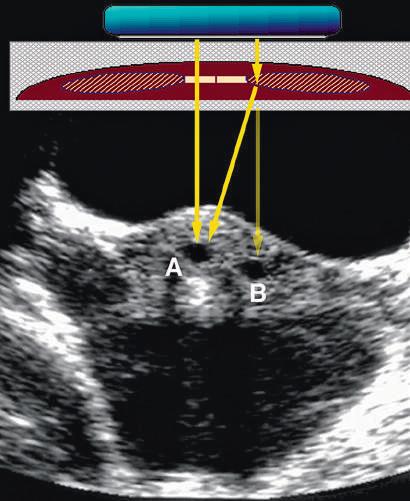

FIG. 1.8 Refraction Artifact. (A) and (B) Production of an artifact by refraction of sound in a transverse scan of the mid abdomen. The direct sound path properly depicts the location of the object. (B) A “ghost image” (red) produced by refraction at the edge of the rectus abdominis muscle. The transmitted and reflected sound travels along the path of the black arrows. The scanner assumes the returning signal is from a straight line (red arrow) and displays the structure at the incorrect location. (C) Axial transabdominal image of the uterus showing a small gestational sac (A) and what appears to be a second sac (B) due to refraction artifact.

Refraction causes bending of the sound beam so that targets not along the axis of the transducer are insonated. Their reflections are then detected and displayed in the image. This may cause structures to appear in the image that actually lie outside the volume the investigator assumes is being examined (see Fig 1.7). Similarly, side lobes may produce confusing echoes that arise from sound beams that lie outside the main ultrasound beam (Fig. 1.28). These side lobe artifacts are of clinical importance because they may create the impression of structures or debris in fluid-filled structures (Fig. 1.29). Side lobes may also result in errors of measurement by reducing lateral resolution. As with most other artifacts, repositioning the transducer and its focal zone or using a different transducer will usually allow the differentiation of artifactual from true echoes.

in what is actually a simple ovarian cyst.